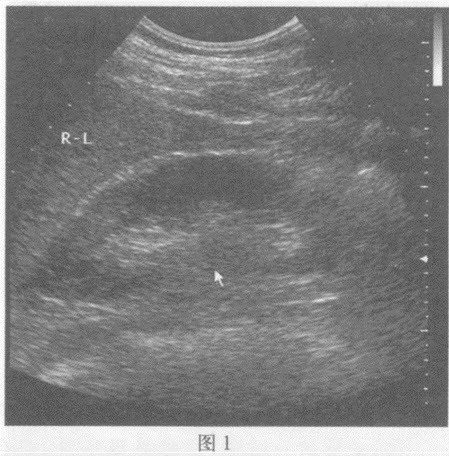

请回答图1、图2箭头所指部位的脏器名称()

A . 图1:左肾;图2:右肾

B . 图1:右肾;图2:左肾

C . 图1:肝脏;图2:脾脏

D . 图1:右肾门;图2:左输尿管

[单选题]请回答图1、图2箭头所指部位的脏器名称:A.图1:左肾;图2:右肾B.图1:右肾;图2:左肾C.图1:肝脏;图2:脾脏D.图1:右肾门;图2:左输尿管